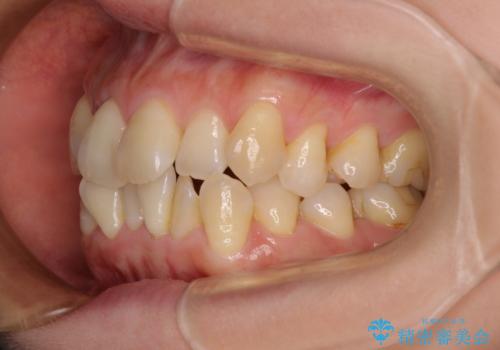

- 上下前歯のデコボコを気にして来院された患者様です。

デコボコは顕著であるものの、口元の突出感は強くないため、非抜歯にて矯正治療を行うこととしました。

元々の叢生と歯肉退縮傾向になる歯肉であったため、ブラックトライアングルが目立つことが想定されました。